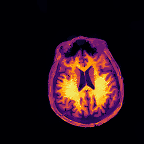

Multi-modality (or multi-channel) imaging is becoming increasingly important and more widely available, e.g. hyperspectral imaging in remote sensing, spectral CT in material sciences as well as multi-contrast MRI and PET-MR in medicine. Research in the last decades resulted in a plethora of mathematical methods to combine data from several modalities. State-of-the-art methods, often formulated as variational regularization, have shown to significantly improve image reconstruction both quantitatively and qualitatively. Almost all of these models rely on the assumption that the modalities are perfectly registered, which is not the case in most real world applications. We propose a variational framework which jointly performs reconstruction and registration, thereby overcoming this hurdle. Numerical results on simulated and real data show the potential of the proposed strategy for various applications in multi-contrast MRI, PET-MR, and hyperspectral imaging: typical misalignments between modalities such as rotations, translations, zooms can be effectively corrected during the reconstruction process. Therefore the proposed framework allows the robust exploitation of shared information across multiple modalities under real conditions.